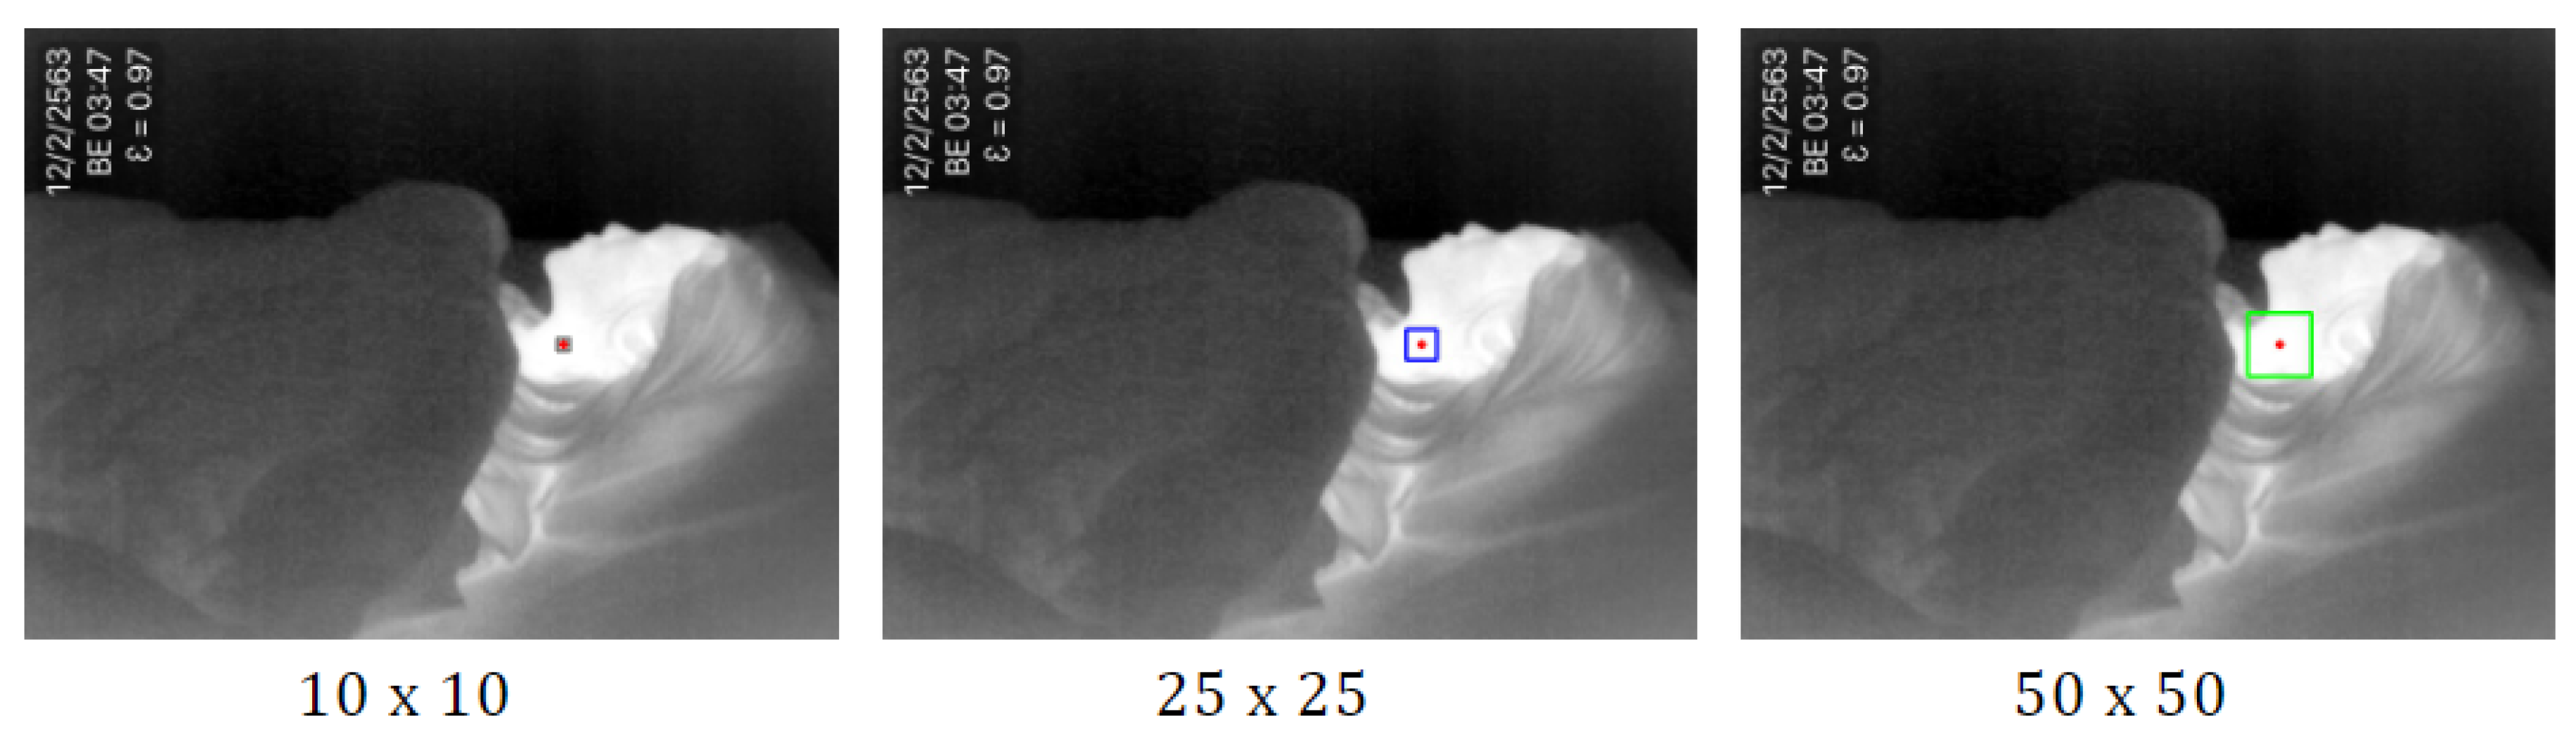

- The highest temperature point is detected by using minMaxLoc. The minMaxLoc function is one of the OpenCV [38] libraries that returns minimum and maximum intensities found in an image with their (x,y) coordinates. It is assumed that the maximum pixel intensities of the thermal image refer to a human’s heat signature that is not covered by a blanket. The maximum pixel intensities found in the image correspond to the highest temperature of the body. We set the pixel to the center of the observation area. Then we draw a rectangle around the pixel, with the size of the square pixels depending on original frame resolution. In [39], the authors compared the ROI size of , , , , and pixels. They found that the size of the ROIs for respiratory rate estimation is usually smaller than that for heart rate estimation. Therefore, in this study, we consider the three different sizes as , , and , as shown in Figure 2. The result in empirical research has shown that the pixels provided the highest accuracy in accordance with the original frame resolution of 640 × 480.